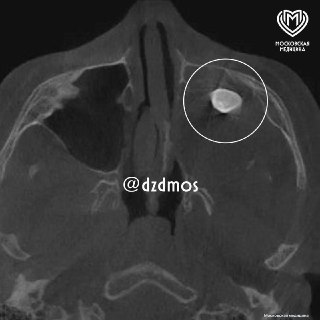

Подросток жаловался на заложенность носа и асимметрию лица. Врачи обнаружили в гайморовой пазухе сформированный зуб. Диагноз — тератома, опухоль, в которой могут развиваться ткани, включая зубы.

В Филатовской больнице хирурги успешно удалили образование. Сейчас пациент дышит свободно, черты лица восстанавливаются.